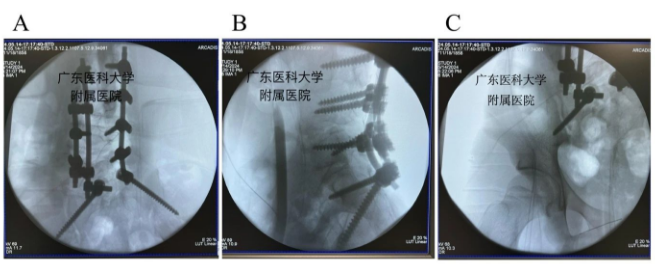

在胡资兵主任医师的指导下,由郑锦畅副主任医师及林瀚主治医生给患者行了经后路腰骶段半椎体切除、L1- L5椎弓根螺钉联合S2骶髂关节螺钉内固定、脊柱侧凸矫形、后外侧植骨融合术,手术过程顺利,术后患者康复迅速,取得满意的矫形效果,让患者挺起脊梁。

经后路腰骶段半椎体切除、L1- L5椎弓根螺钉联合S2骶髂关节螺钉内固定、脊柱侧凸矫形、后外侧植骨融合术